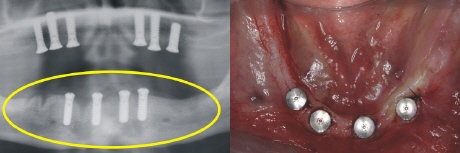

Implantation

Sechs strategisch günstig positionierte Implantate wurden im Oberkiefer eingebracht, um nach der Einheilung optimalen Halt für die Prothese zu gewährleisten (gelber Kreis im Röntgenbild).

Im Unterkiefer können die vier Implantate (Standardversorgung) im vorderen Kieferbereich eingebracht werden (gelber Kreis im Röntgenbild).